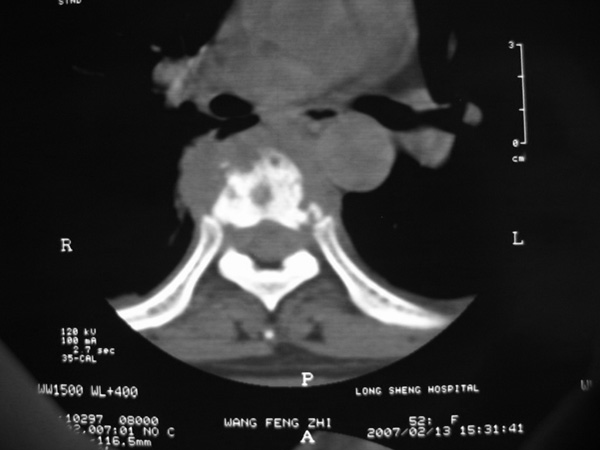

女,45岁,胸背部疼痛2个月。t6、7胸椎病变。

椎旁肿胀的软组织内可见气泡影,对脊柱的化脓性和结核性的鉴别有帮助吗?

胸椎结核伴冷脓肿形成且侵入椎管。